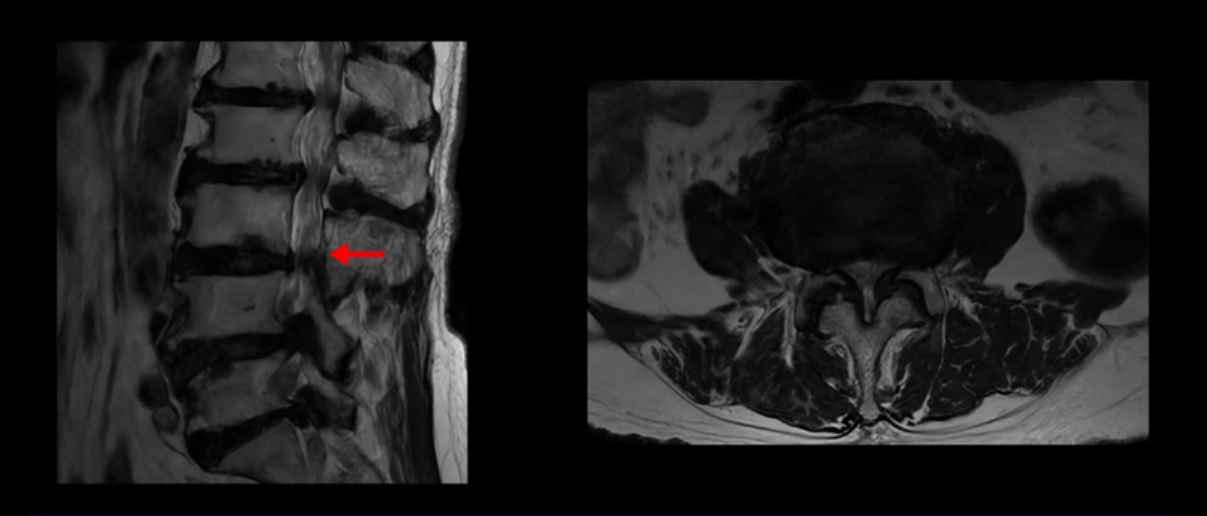

MRI 보시면 (2-8) 허리의 5마디가 전부 다 심하게 퇴행되어 있습니다.

5마디 전부 다 심한 중심성 협착이 있습니다.

4번 5번,

5번 6번

이렇게 모두 다 심하게 막히는 경우는 드문데요. 또한 오른쪽, 왼쪽 신경이 빠져나가는 추간공도 다 심하게 막혀있습니다.

오른쪽, 왼쪽 이렇게 신경 구멍들이 다 좁아지고 신경이 눌리니까 양쪽 다리가 발바닥까지 아파서 걷기 어렵고 양쪽 발이 10년 넘게 시린 겁니다. 당연히 수술해서 눌린 신경을 풀어줘야 한다고 들으셨는데요. 이런 환자분을 어떻게 수술 없이 치료할까요? 지금부터 설명해 드립니다.

실제로 수많은 논문에서 70세 이후 MRI로 협착이 보여도 아프지 않은 무증상 협착이 많다고 설명합니다. 협착이 있어도 안 아픈 사람들이 많다는데, 이게 왜 그럴까요? 근육 기능이 정상적이고 좋은 사람들은 근육이 허리를 잘 지지해 주니까 협착이 있어도 신경이 덜 눌리거나 안 눌리는 겁니다. 즉 근육이 좋으면 신경이 덜 눌리고 근육이 좋아지면 협착증이 좋아지는 겁니다. 그래서 저희가 근육 재활치료를 통해 근육의 기능을 회복시키면서 동시에 신경의 기능을 회복시키는 치료를 하는 겁니다. 이런 분들이 근육 재활치료를 통해서 협착증 증상이 좋아진다면 이런 분들의 협착증도 아프지 않은 무증상 협착으로 바뀌게 되는 겁니다.